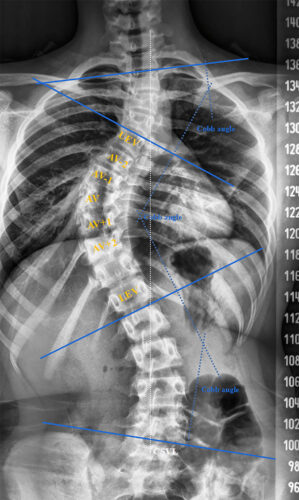

يعاني العديد من الأطفال والمراهقين من اعوجاج العمود الفقري (Scoliosis)، ويطرح الأهل سؤالًا مهمًا: ما هو أفضل سن لعلاج اعوجاج العمود الفقري عند الأطفال والمراهقين؟ وهل هناك فترة زمنية مثالية تمنع تفاقم الانحناء؟ في هذا المقال، سنقدّم إجابة شاملة، مبسطة، وعلمية تساعد الأهل على فهم أفضل توقيت للعلاج، وأنواع التدخلات الممكنة، وأهمية المتابعة الدورية.

أفضل سن لعلاج اعوجاج العمود الفقري عند الأطفال والمراهقين هو أثناء النمو السريع للأطفال والمراهقين.

الكشف المبكر يمنع تطور الانحناء ويقلل الحاجة للجراحة.